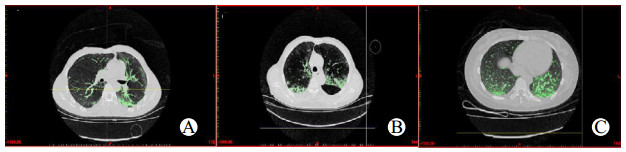

1.2.2 定量分析患者胸部HRCT患者胸部HRCT通过GE工作台(Advantage Workstation 4.4; GE Healthcare)由一名工作15年的放射科医生进行三维重建,该医生仅行三维重建,不能阅读临床资料。建模步骤可以分为4步:读取图像、提取轮廓、选择热区、生成三维模型。选择热区按照Oikonomou等[12]所采取的方案,本研究把肺内病变根据CT值分为四个部分:过度通气区(CT阈值:-1000HU到-901HU)、正常通气区(CT阈值:-900HU到-501HU)、通气减低区(CT阈值:-500HU到-101HU)和不通气区(CT阈值:-100HU到100HU)。在本研究中主要观察肺磨玻璃影改变对急性PQ中毒患者预后的影响,而磨玻璃影改变可以近似看作为通气减低区域。入组患者在入院第3、5、7天行肺HRCT检查,调取患者原始影像资料,导入工作台行三维重建。选择CT阈值-500HU至-101HU为磨玻璃影改变热区,标记热区颜色为绿色,通过蒙版编辑把肺外相同CT值的其他组织部分剪掉(图 1~2)。同样的方法标记过度通气区、正常通气区和不通气区,并蒙版编辑肺外区域后,计算四个区域的总和即肺的容积,最后计算磨玻璃样体积占肺的体积比(V%GGOs)来量化分析磨玻璃影。

| A~C分别代表第3、5、7天;绿色为所选热区(CT值-500 HU至-101 HU) 图 1 生存组同一病例第3、5、7天GGOs改变 Fig 1 Changes of GGOs on the 3rd, 5th and 7th day in the same person of the survival group |